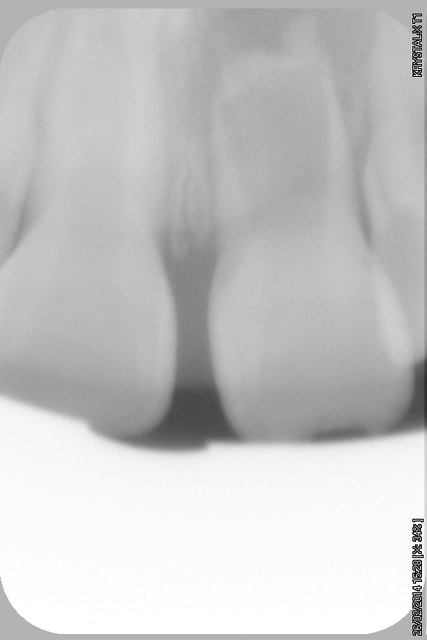

- radios en pièce jointe

- Déterminer par cone beam l'intégrité des parois radiculaires (Y-a-t-il une communication endo paro ou non?)

- Essayer de conserver ce qui reste de la racine par un ttt CaOH ou obturation radiculaire à la biodentine ou au MTA blanc?

- stopper ce qui est vraisemblablement une résorption inflammatoire (faut pas trainer!)